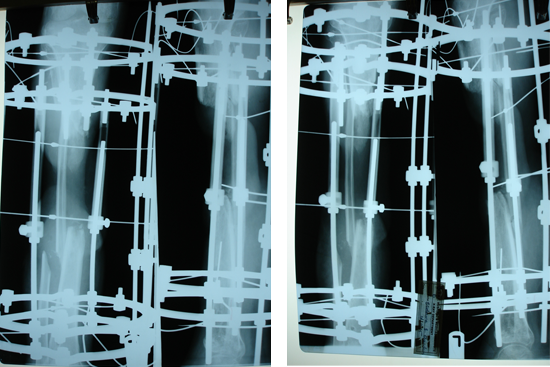

Tibialisation Of Fibula

Shankar Giri

Sudama

Wagh